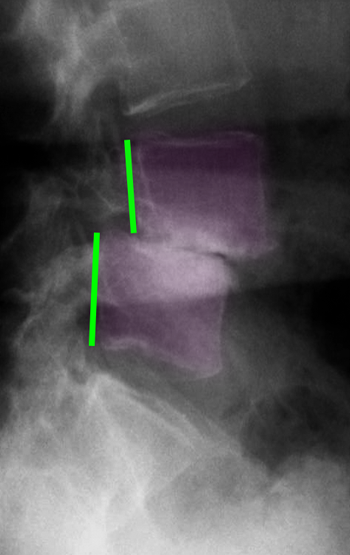

Εκφυλιστική σπονδυλολίσθηση Ο4-Ο5. Πλήρης σχεδόν εκφύλιση του μεσοσπονδυλίου δίσκου με καθίζηση του μεσοσπονδυλίου διαστήματος. |